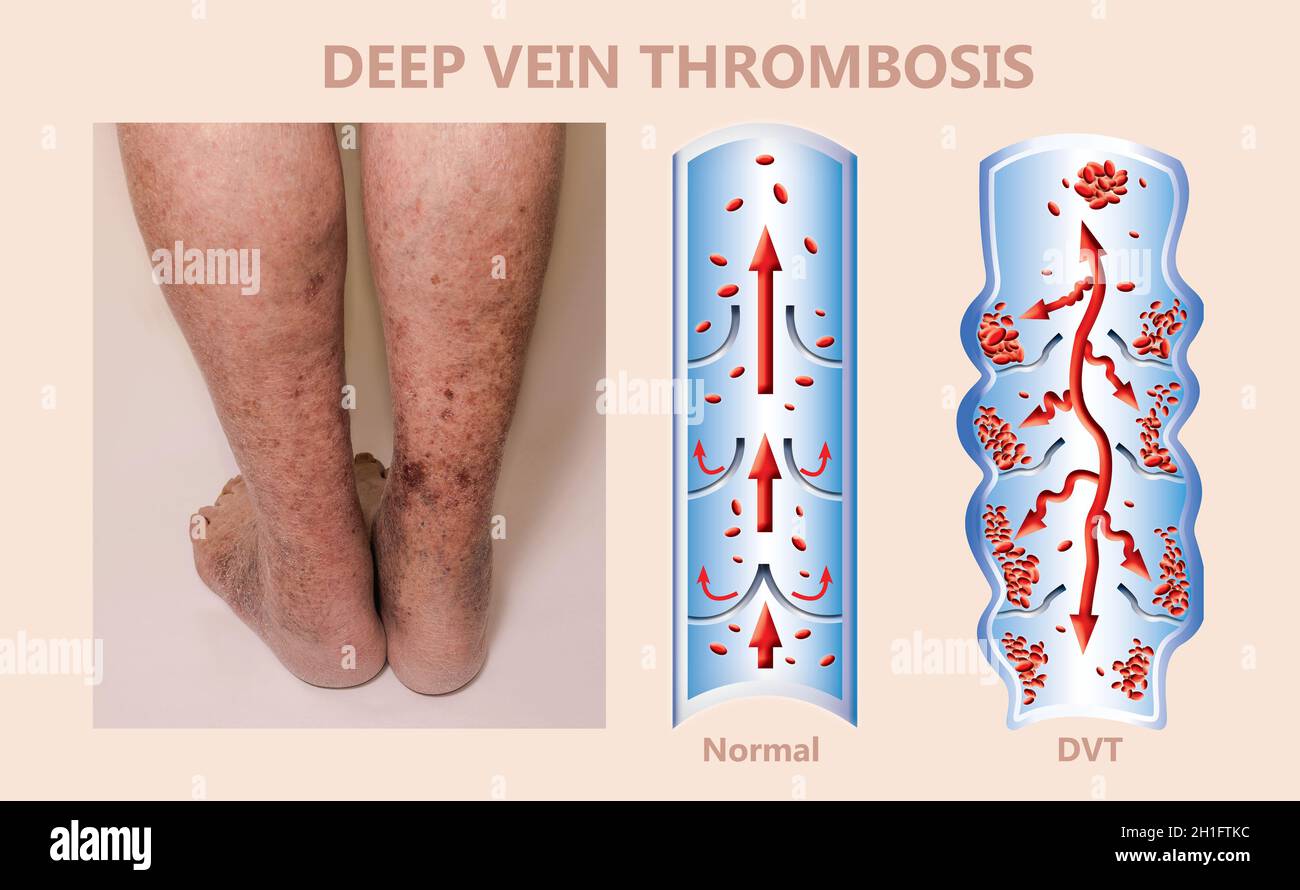

RM2H1FTKC–Syndrome mécanisme, thrombose veineuse profonde ou embolie pulmonaire, thrombose ou PE, thrombose coronaire, illustration du schéma de jambes mâle

RFRN7ABR–Syndrome mécanisme, thrombose veineuse profonde ou d'une thrombose veineuse profonde, embolie pulmonaire, thrombose coronaire, schéma

RFRN7AAX–Syndrome mécanisme, thrombose veineuse profonde ou d'une thrombose veineuse profonde, embolie pulmonaire, thrombose coronaire, schéma